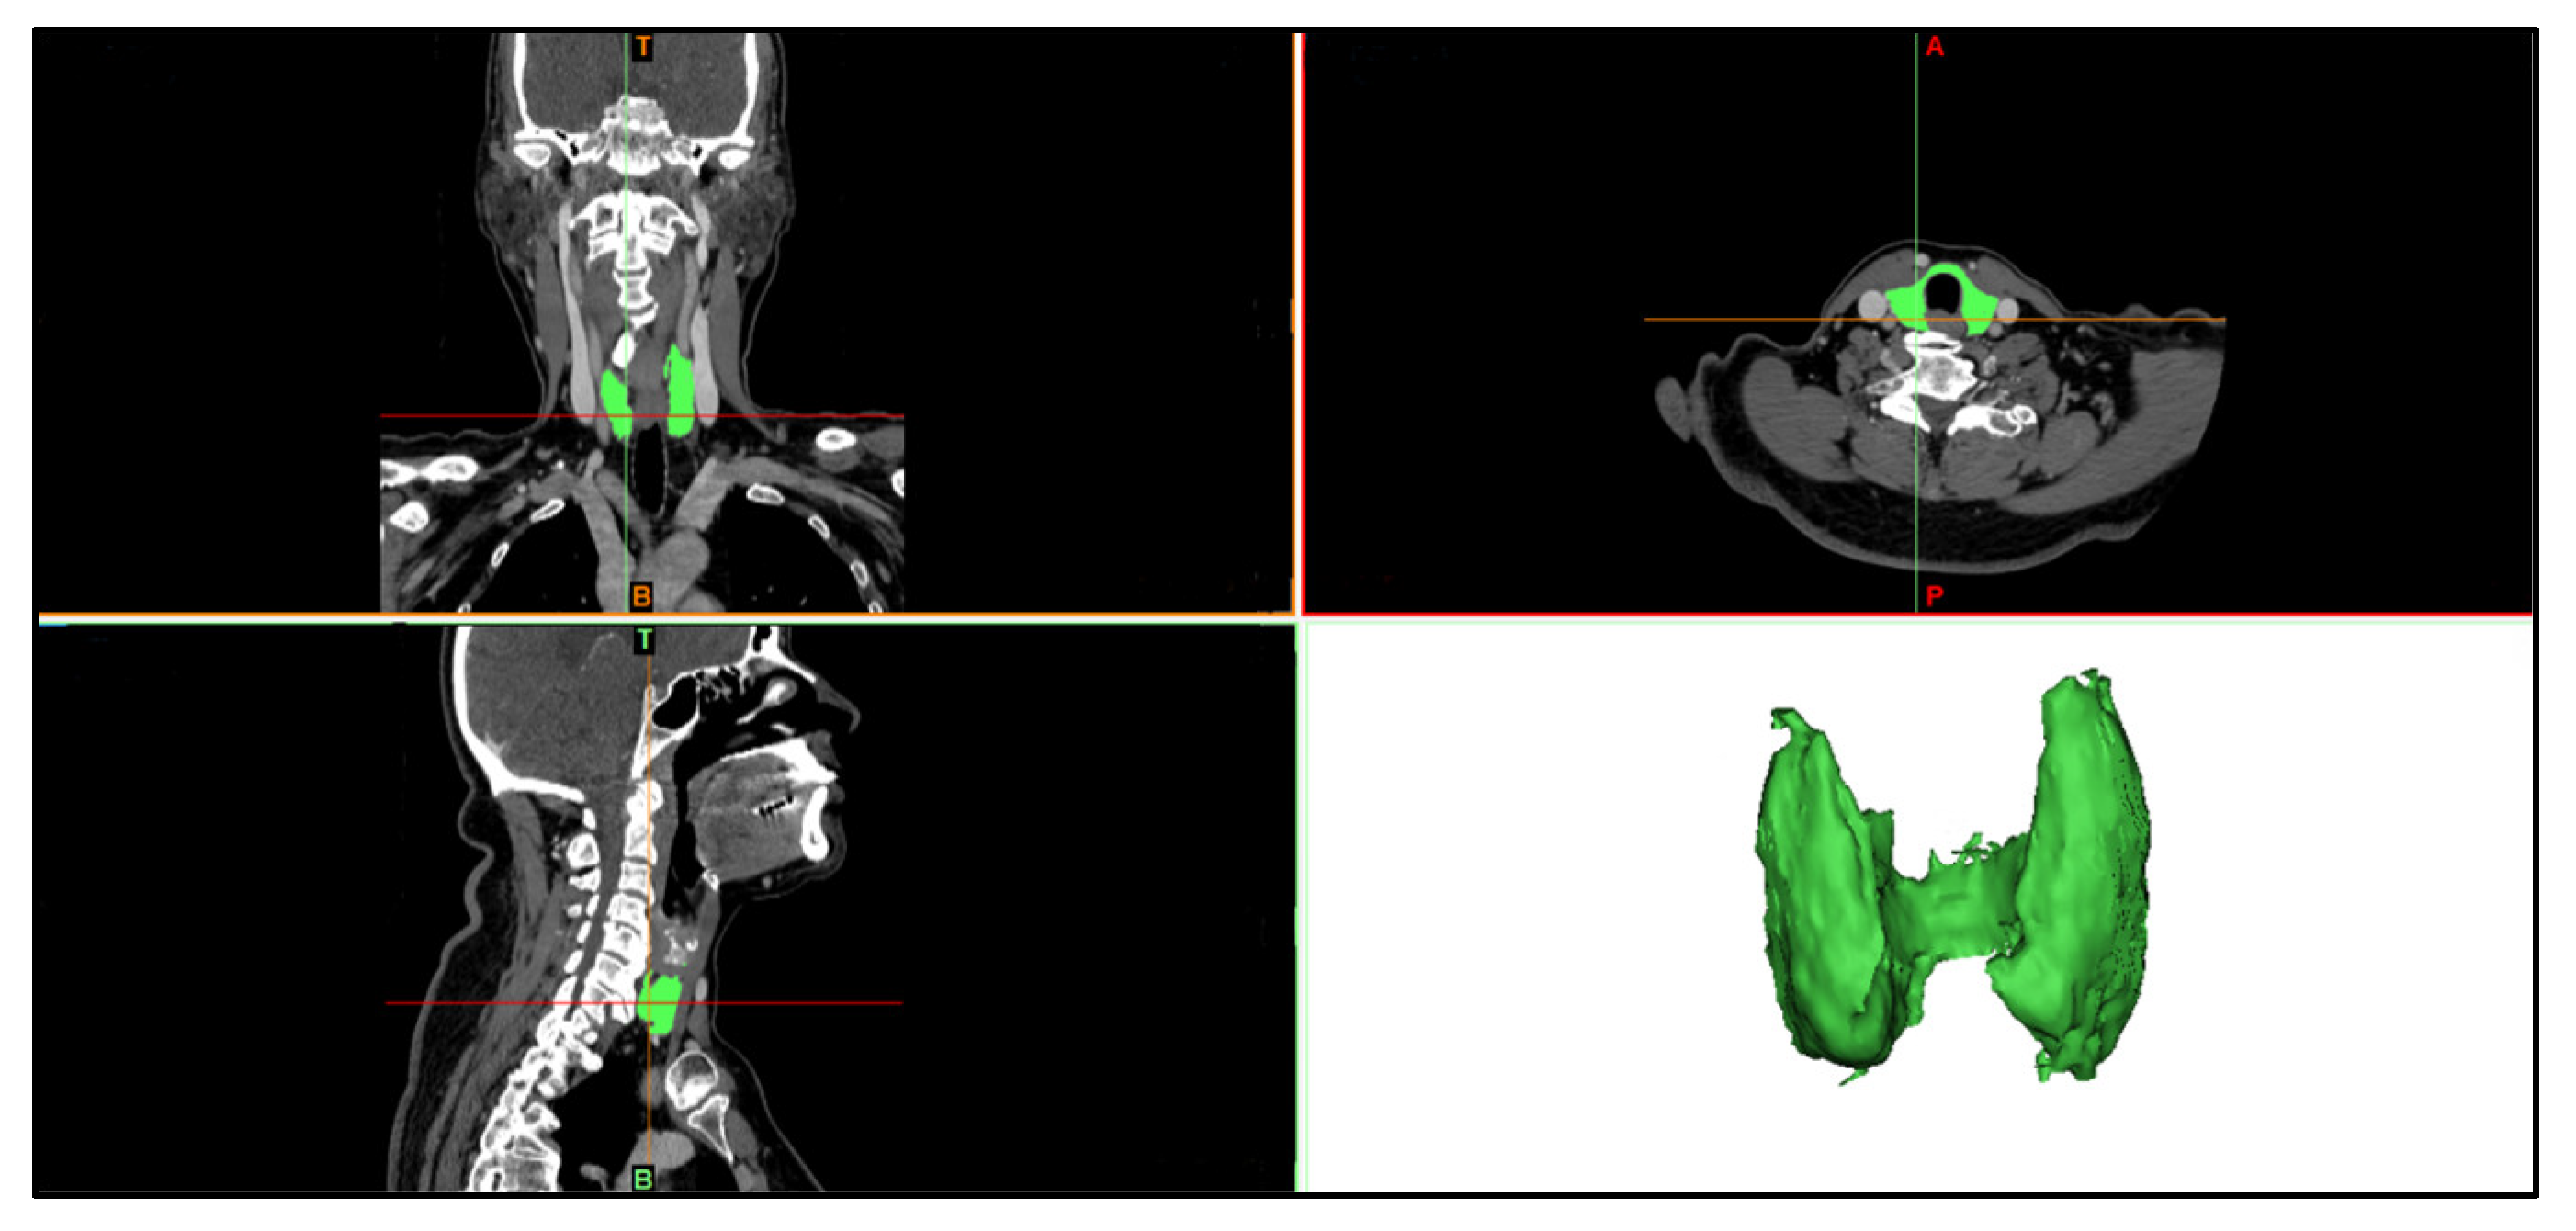

Through CT images, it was possible to identify the thyroid gland and other structures in the anatomical sections (i.e., coronal, sagittal, and axial), as illustrated in Figure 14, evidencing the anatomical segmentation of the analyzed region. The 3D thyroid selection and reconstruction are highlighted in green in this image.

Figure 14.

Illustration of a set of CT images visualized in the MIMICS software, to allow for the segmentation and 3D reconstruction of the thyroid geometry in the neck region.